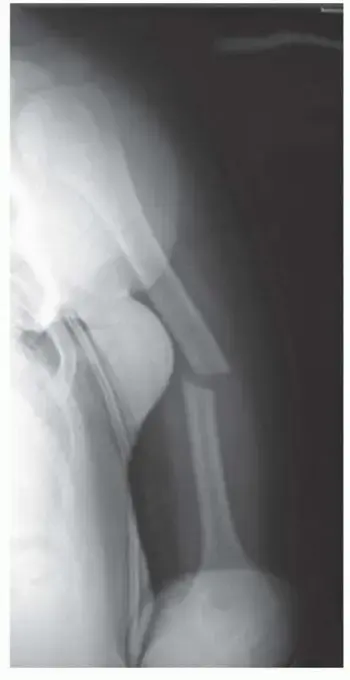

العلاج الجراحي تثبيت كسور عظم العضد بالصفائح (Plate Fixation)

في بعض الحالات، يكون التدخل الجراحي ضروريًا وحاسمًا لضمان التئام الكسر بشكل صحيح واستعادة الوظيفة الكاملة للذراع. تُعد عملية التثبيت بالصفائح والمسامير (Plate Fixation) من أكثر الطرق الجراحية فعالية وشيوعًا لكسور جذع العضد.

عملية التثبيت بالصفائح والمسامير (Plate Fixation):

خطوات العملية بشكل مبسط:

1. التخدير: يتم تخدير المريض بشكل كامل.

2. الشق الجراحي: يقوم الجراح بعمل شق جراحي على طول الذراع للوصول إلى العظم المكسور. يعتمد موقع وطول الشق على موقع ونوع الكسر.

3. إعادة المحاذاة (Reduction): يتم إعادة تجميع قطع العظم المكسور ووضعها في محاذاتها الطبيعية قدر الإمكان.

4. تثبيت الصفائح والمسامير:

* يتم استخدام صفائح معدنية خاصة (مصنوعة عادة من التيتانيوم أو الفولاذ المقاوم للصدأ) مصممة لتناسب شكل العظم.

* تُثبت هذه الصفائح على سطح العظم باستخدام مسامير معدنية صغيرة، تمر عبر الصفيحة والعظم لتثبيت الأجزاء المكسورة بإحكام.

* تعمل الصفائح والمسامير كدعامات داخلية تحافظ على العظم في مكانه الصحيح بينما يلتئم.

* هناك أنواع مختلفة من الصفائح، مثل الصفائح الضاغطة (Compression plates) والصفائح القفلية (Locking plates)، التي توفر استقرارًا فائقًا حتى في العظام ذات الجودة الضعيفة.

5. إغلاق الجرح: بعد التأكد من استقرار الكسر، يتم إغلاق الأنسجة والعضلات والجلد بالغرز.